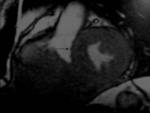

Methods: Twenty-two patients referred to our department with a suspected cardiac mass, previously detected by cardiac ultrasound, were evaluated by CT (12 patients) and MRI (4 patients). Six patients were examined by both modalities. In 2 cases of staging of a known primary neoplasm and one case of a suspected epicardiac lesion, positron emission tomography (PET-CT) was performed. The CT cardiac examinations were performed using a 16-slice multislice scanner with ECG gating. The MRI examination was performed on a 1.5 Tesla MRI scanner using an ECG-gated cardiac protocol and the PET-CT examination was performed on an integrated PET-CT four-slice scanner, using 370 mMBq of fluorodeoxyglucose.

Results: Twenty-two cardiac masses were successfully detected and their characteristics adequately delineated, including eight myxomas, one angiosarcoma, one ventricular lymphoma, one endocardiac metastasis, one epicardiac paraganglioma, and 10 cases of intracardiac thrombi.